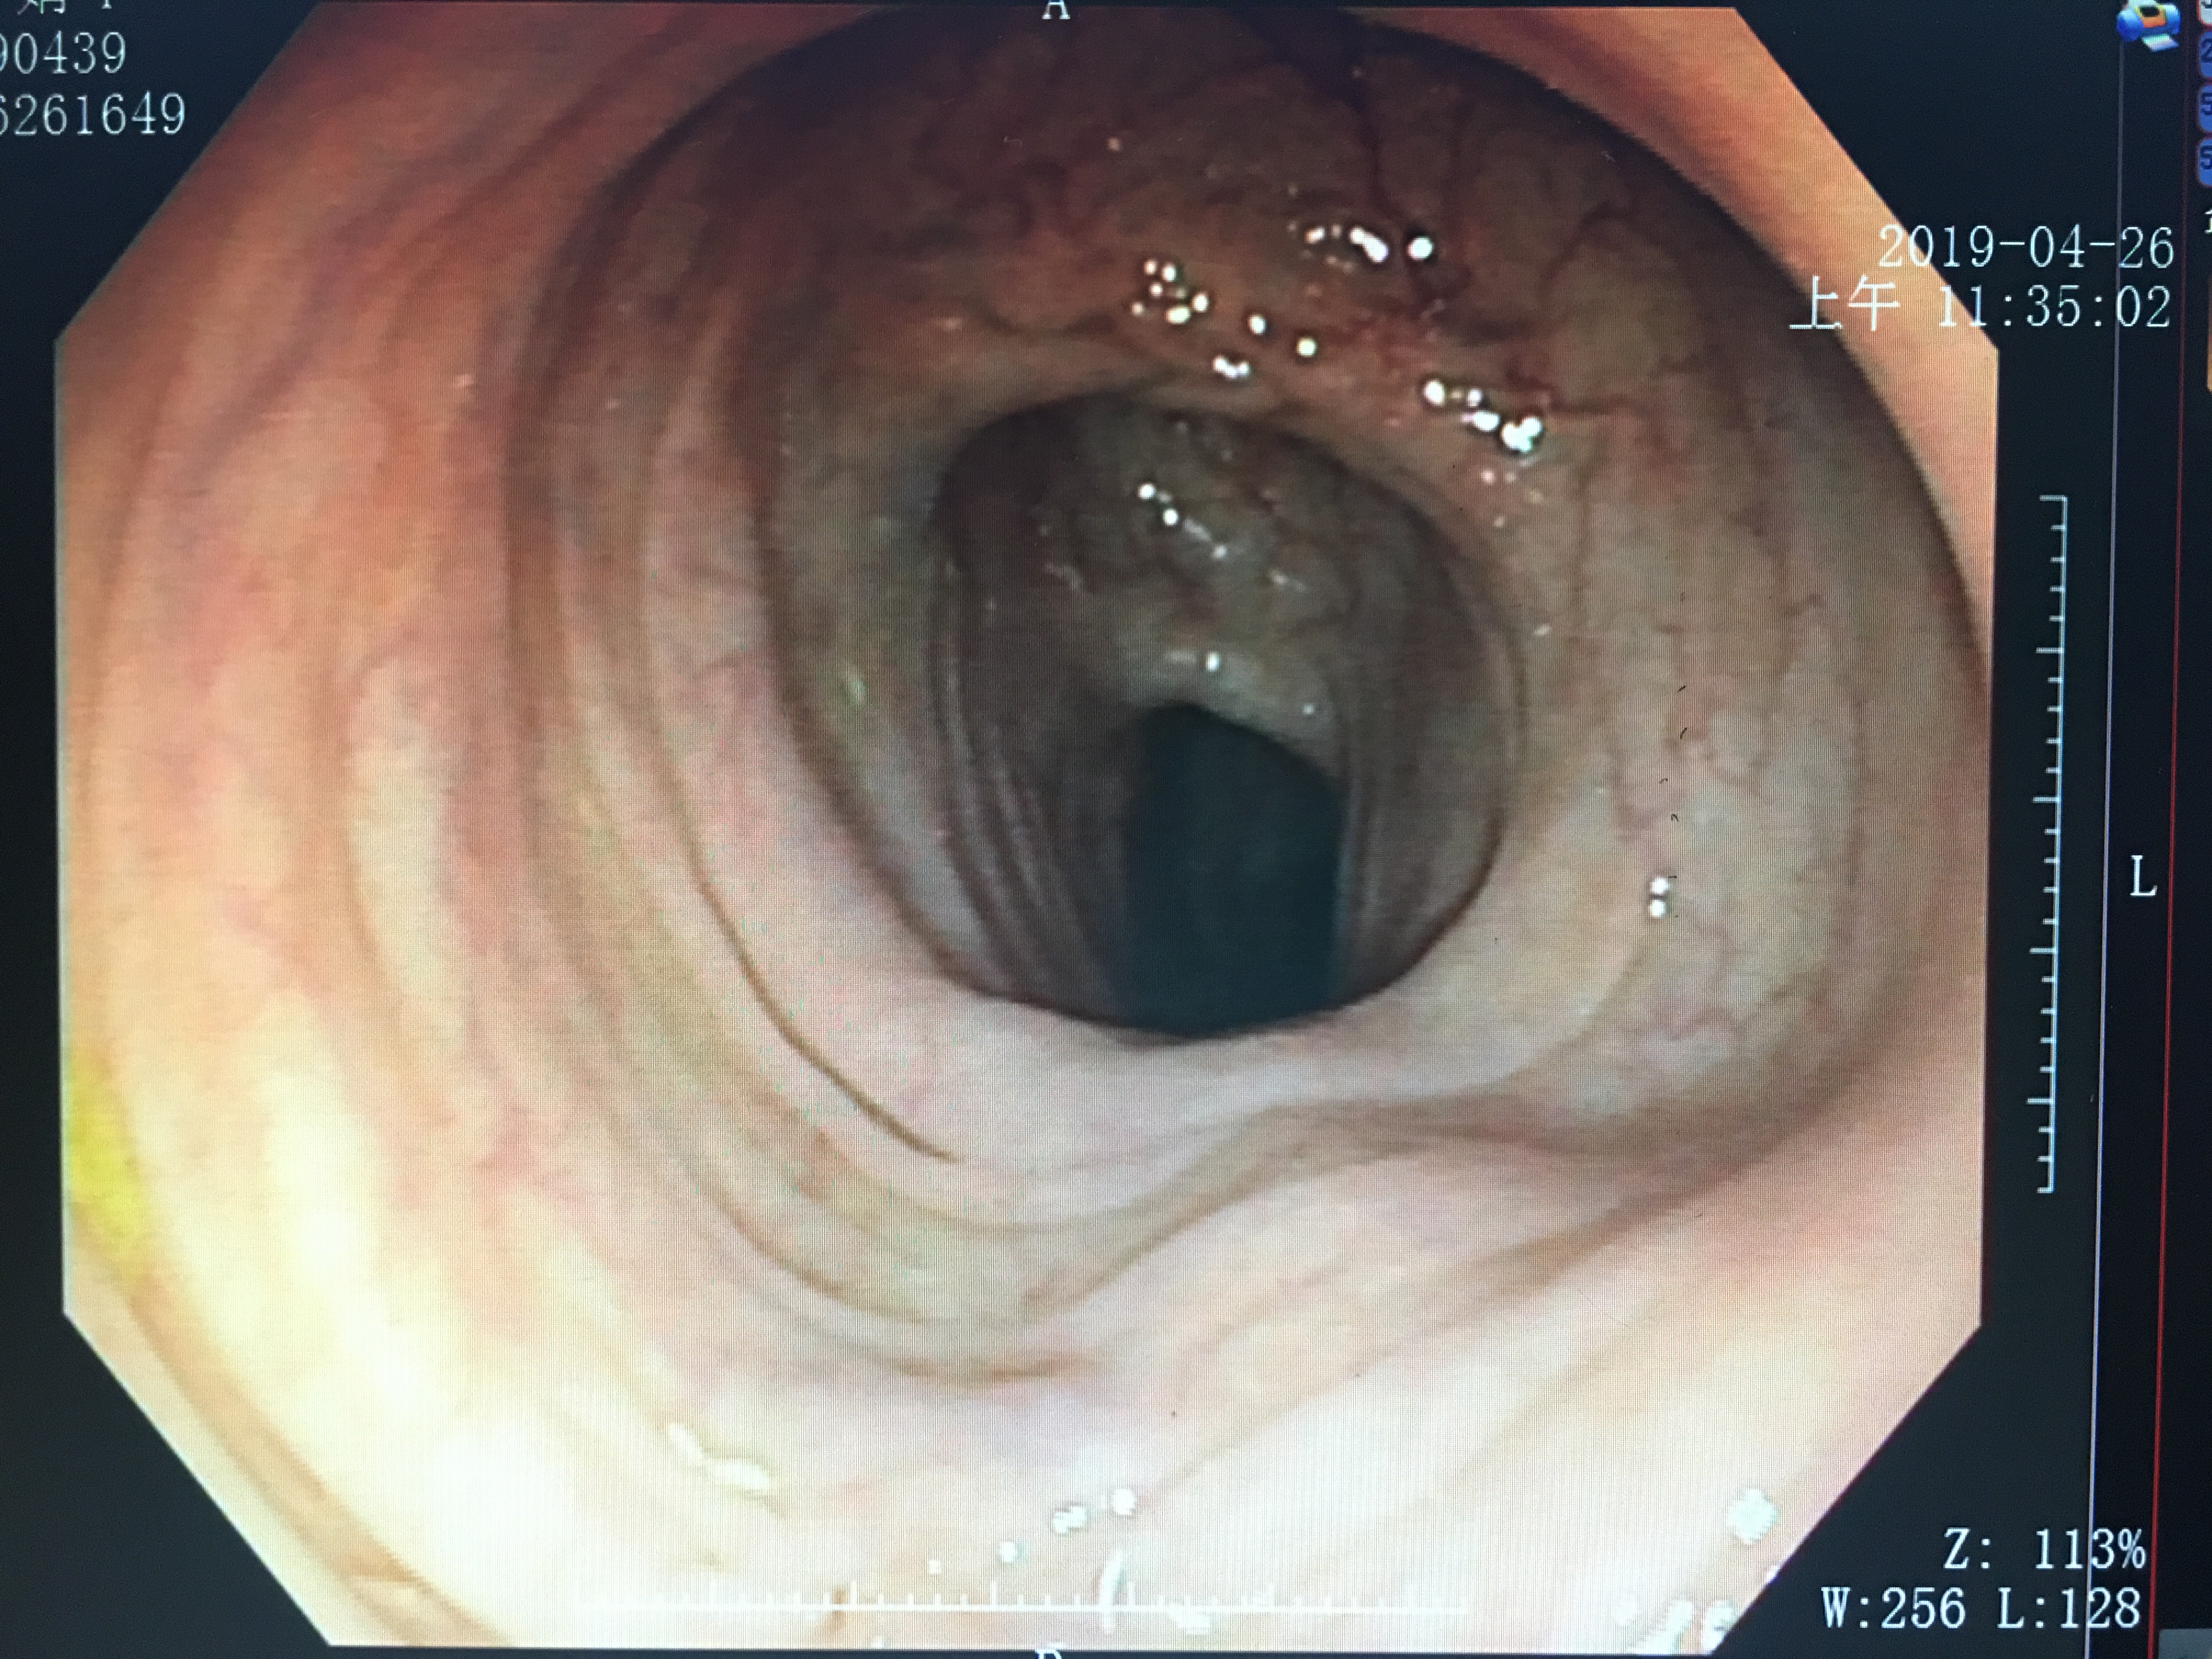

不信?先看看正常的镜下“高清图”:

准备的较好的胃镜下图像

经过一整晚的禁食,胃部的食物已经排空。在第二天早上,因为还没进食,胃中也不会分泌过多的胃酸,所以可以看到比较清晰的“景象”。